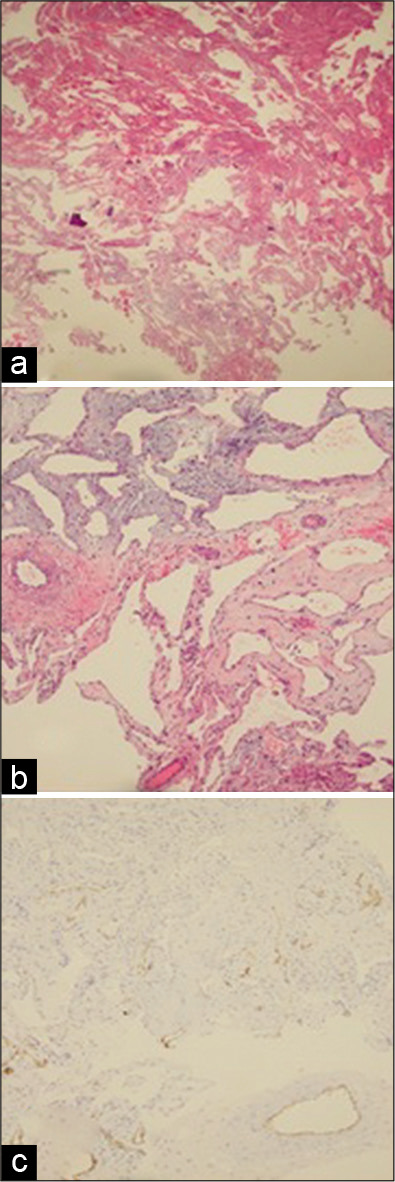

在头颈外科医生的配合下,采用内窥镜下经鼻蝶(EET)入路接近病变。在鞍底开放过程中,遇到一个暗红色的坚硬病变,似乎是血管性的。在试图切除病灶时遇到了过度出血。术中冰冻切片活检证实了病变的血管性质,排除了垂体病变。考虑到病变的未知性质、高血管性和出血倾向,决定对病变进行次全切除术,目的是减少肿块效应,而不会出现并发症。特别注意获得完全止血。随后的组织病理学检查证实了CCH的诊断【图3】。

图3:组织病理学切片图像。(a和b)来自标本的切片显示肿瘤由多个大血管通道组成,这些通道由内皮细胞排列,并被疏松的纤维组织和局部淋巴细胞浸润分开。它们中的大多数在腔内含有红细胞。很少有纤维化和局部螺纹化的区域被注意到。未见垂体组织。检查的活检材料中没有恶性肿瘤的证据。(c) CD34免疫组织化学染色,突出小毛细血管。